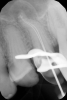

Marina_A Опубликовано 6 июня, 2013 Поделиться Опубликовано 6 июня, 2013 Пациентка пришла с целью санации).Я посмотрела на снимок очередного зуба и ахнула Но все оказалось не так плохо, нам удалось пройти каналы. ну и конечно же, как без паффа? зато какой четкий знак вопроса! 8 Ссылка на комментарий

Kivilgar Опубликовано 6 июня, 2013 Поделиться Опубликовано 6 июня, 2013 Пациентка пришла с целью санации).Я посмотрела на снимок очередного зуба и ахнула 1.PNG Но все оказалось не так плохо, нам удалось пройти каналы.2.PNG ну и конечно же, как без паффа? зато какой четкий знак вопроса! 3.PNGЗдорово получилось. Какими файлами? Ссылка на комментарий